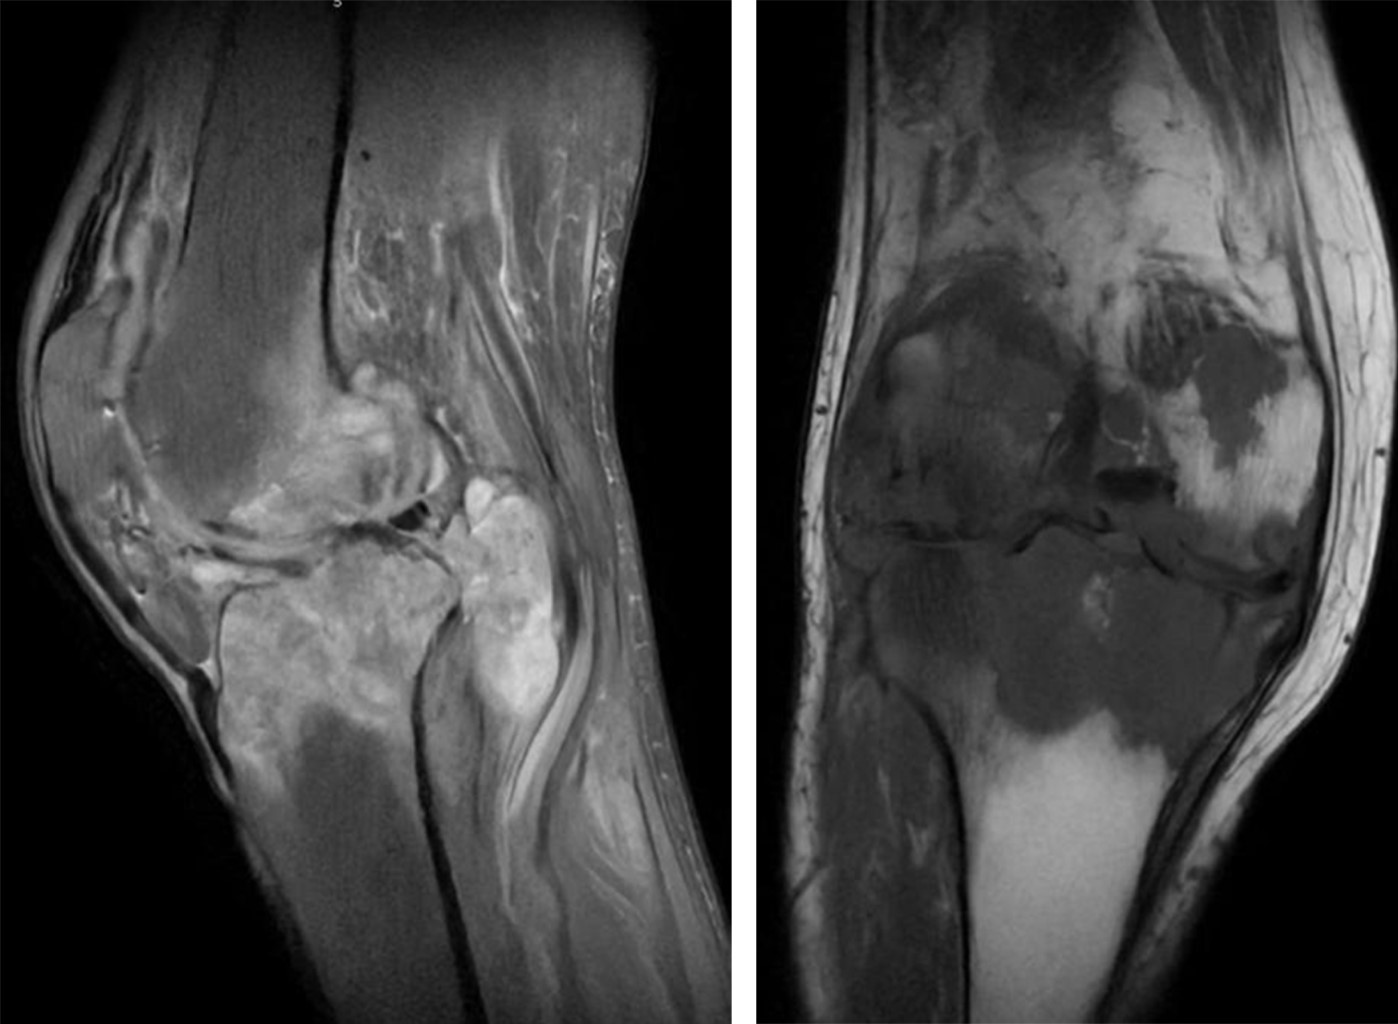

Candida glabrata osteomyelitis with septic arthritis in right knee

osteomyelitis, Candida glabrata, Baker\'s cyst, septic arthritis.

Osteomyelitis caused by Candida glabrata is an uncommon pathology that can cause severe complications if not detected and treated opportunely; it represents a diagnostic and therapeutic challenge due to the scarce reported information. We present the case of a 57-year-old woman with long-term, uncontrolled type 2 diabetes who presents osteomyelitis and septic arthritis caused by C. glabrata in the right knee after a direct trauma that later required three surgical interventions without remission. We describe the diagnostic methodology and evolution of the case during the patient's hospital stay.

Figure 2

Figure 3